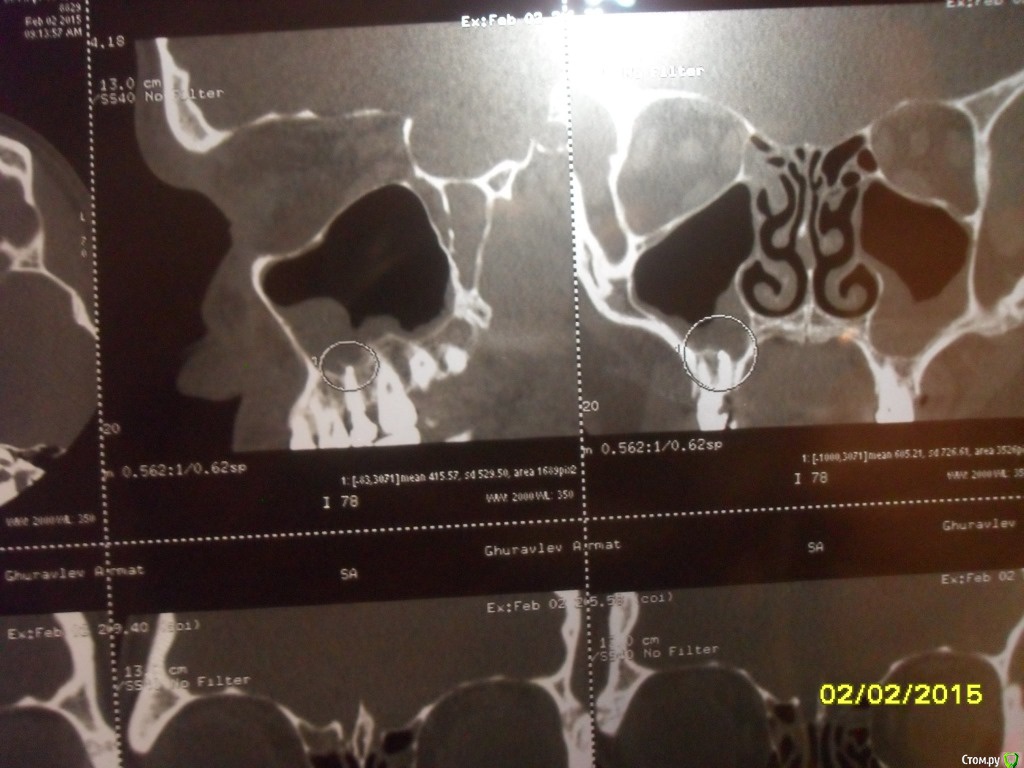

asin Опубликовано 7 февраля, 2015 Поделиться Опубликовано 7 февраля, 2015 (изменено) Добрый день всем, прошу у вас помощи или совета. Ездил на МСКТ пазух носа нашли пломбировочный материал, сломанный инструмент и кисту в правой пазухе 5 зуб. у меня его делали там штифт стоит канал пломбирован((((( мучает хронический катаральный гайморит((((( снимки прилагая может быть подскажите что мне делать.советуют дергать зуб с корнем и потом ушивать потому что откроется вход в пазуху....https://yadi.sk/d/nfWCumo7eU5ST тут образ диска МСКт... если кто то посмотрит буду признателен Изменено 7 февраля, 2015 пользователем asin Ссылка на комментарий